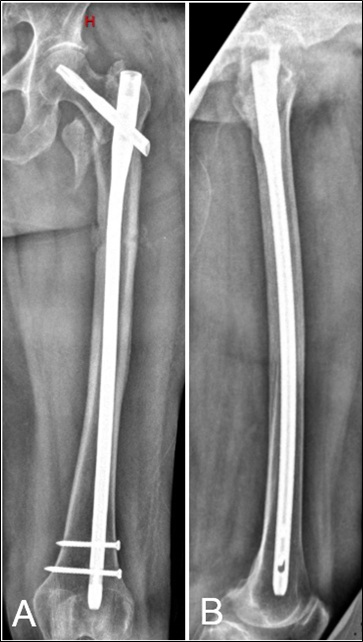

Penetración de la cortical anterolateral en fracturas de fémur proximal tratadas con clavos endomedulares cortos Reporte de dos casos. [Penetration of anterior-lateral cortex in proximal femur fractures treated with short intramedullary nails Report of two cases].

7. Ostrum RF, Levy MS. Penetration of the distal femoral anterior cortex during intramedullary nailing for subtrochanteric fractures: a report of three cases. J Orthop Trauma 2005;19:656-60.

9. Egol KA, Chang EY, Cvitkovic J, Kummer FJ, Koval KJ. Mismatch of current intramedullary nails with the anterior bow of the femur. J Orthop Trauma 2004;18:410-5.